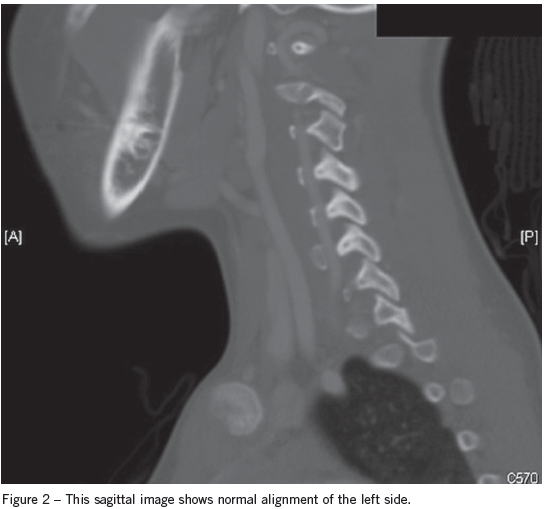

The next day the patient’s CT scan was evaluated by the attending radiologist, who found a right C3-4 facet dislocation. The child was called back to the ED for reevaluation. A neck CT scan with contrast demonstrated a jumped facet at C3, and a kink in the vertebral artery (Figure 1) and normal alignment of the left side (Figure 2).